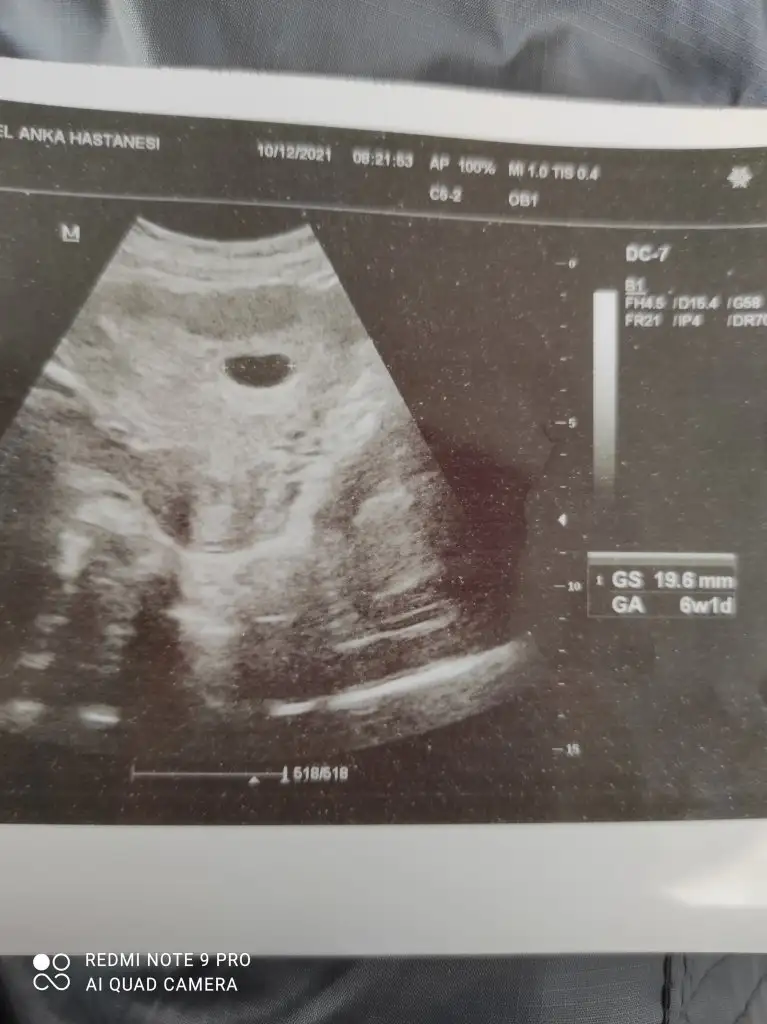

Masallah cnm saglikla gelsin bebegin ramzi teori 7 haftalik olunca tam soyleniyor cnm yani bebegin konumuna göre kalp atışını duydugunda insllah at bakalim ozaman cnmM Maviayyy G Guzel Aslan R rana20 L Lilarengim1Expresso 4melek1anne hanımlar biz 6 hafta 1 günlük olduk buda kesemiz henüz bebeği göremedik haftaya kalp atışını duymaya gidecez inşallah ramzi teorisi ne göre tahmininiz varmı acaba ? Dr alakası yok dedi bana ama bilemiyorum Eki Görüntüle 2967837